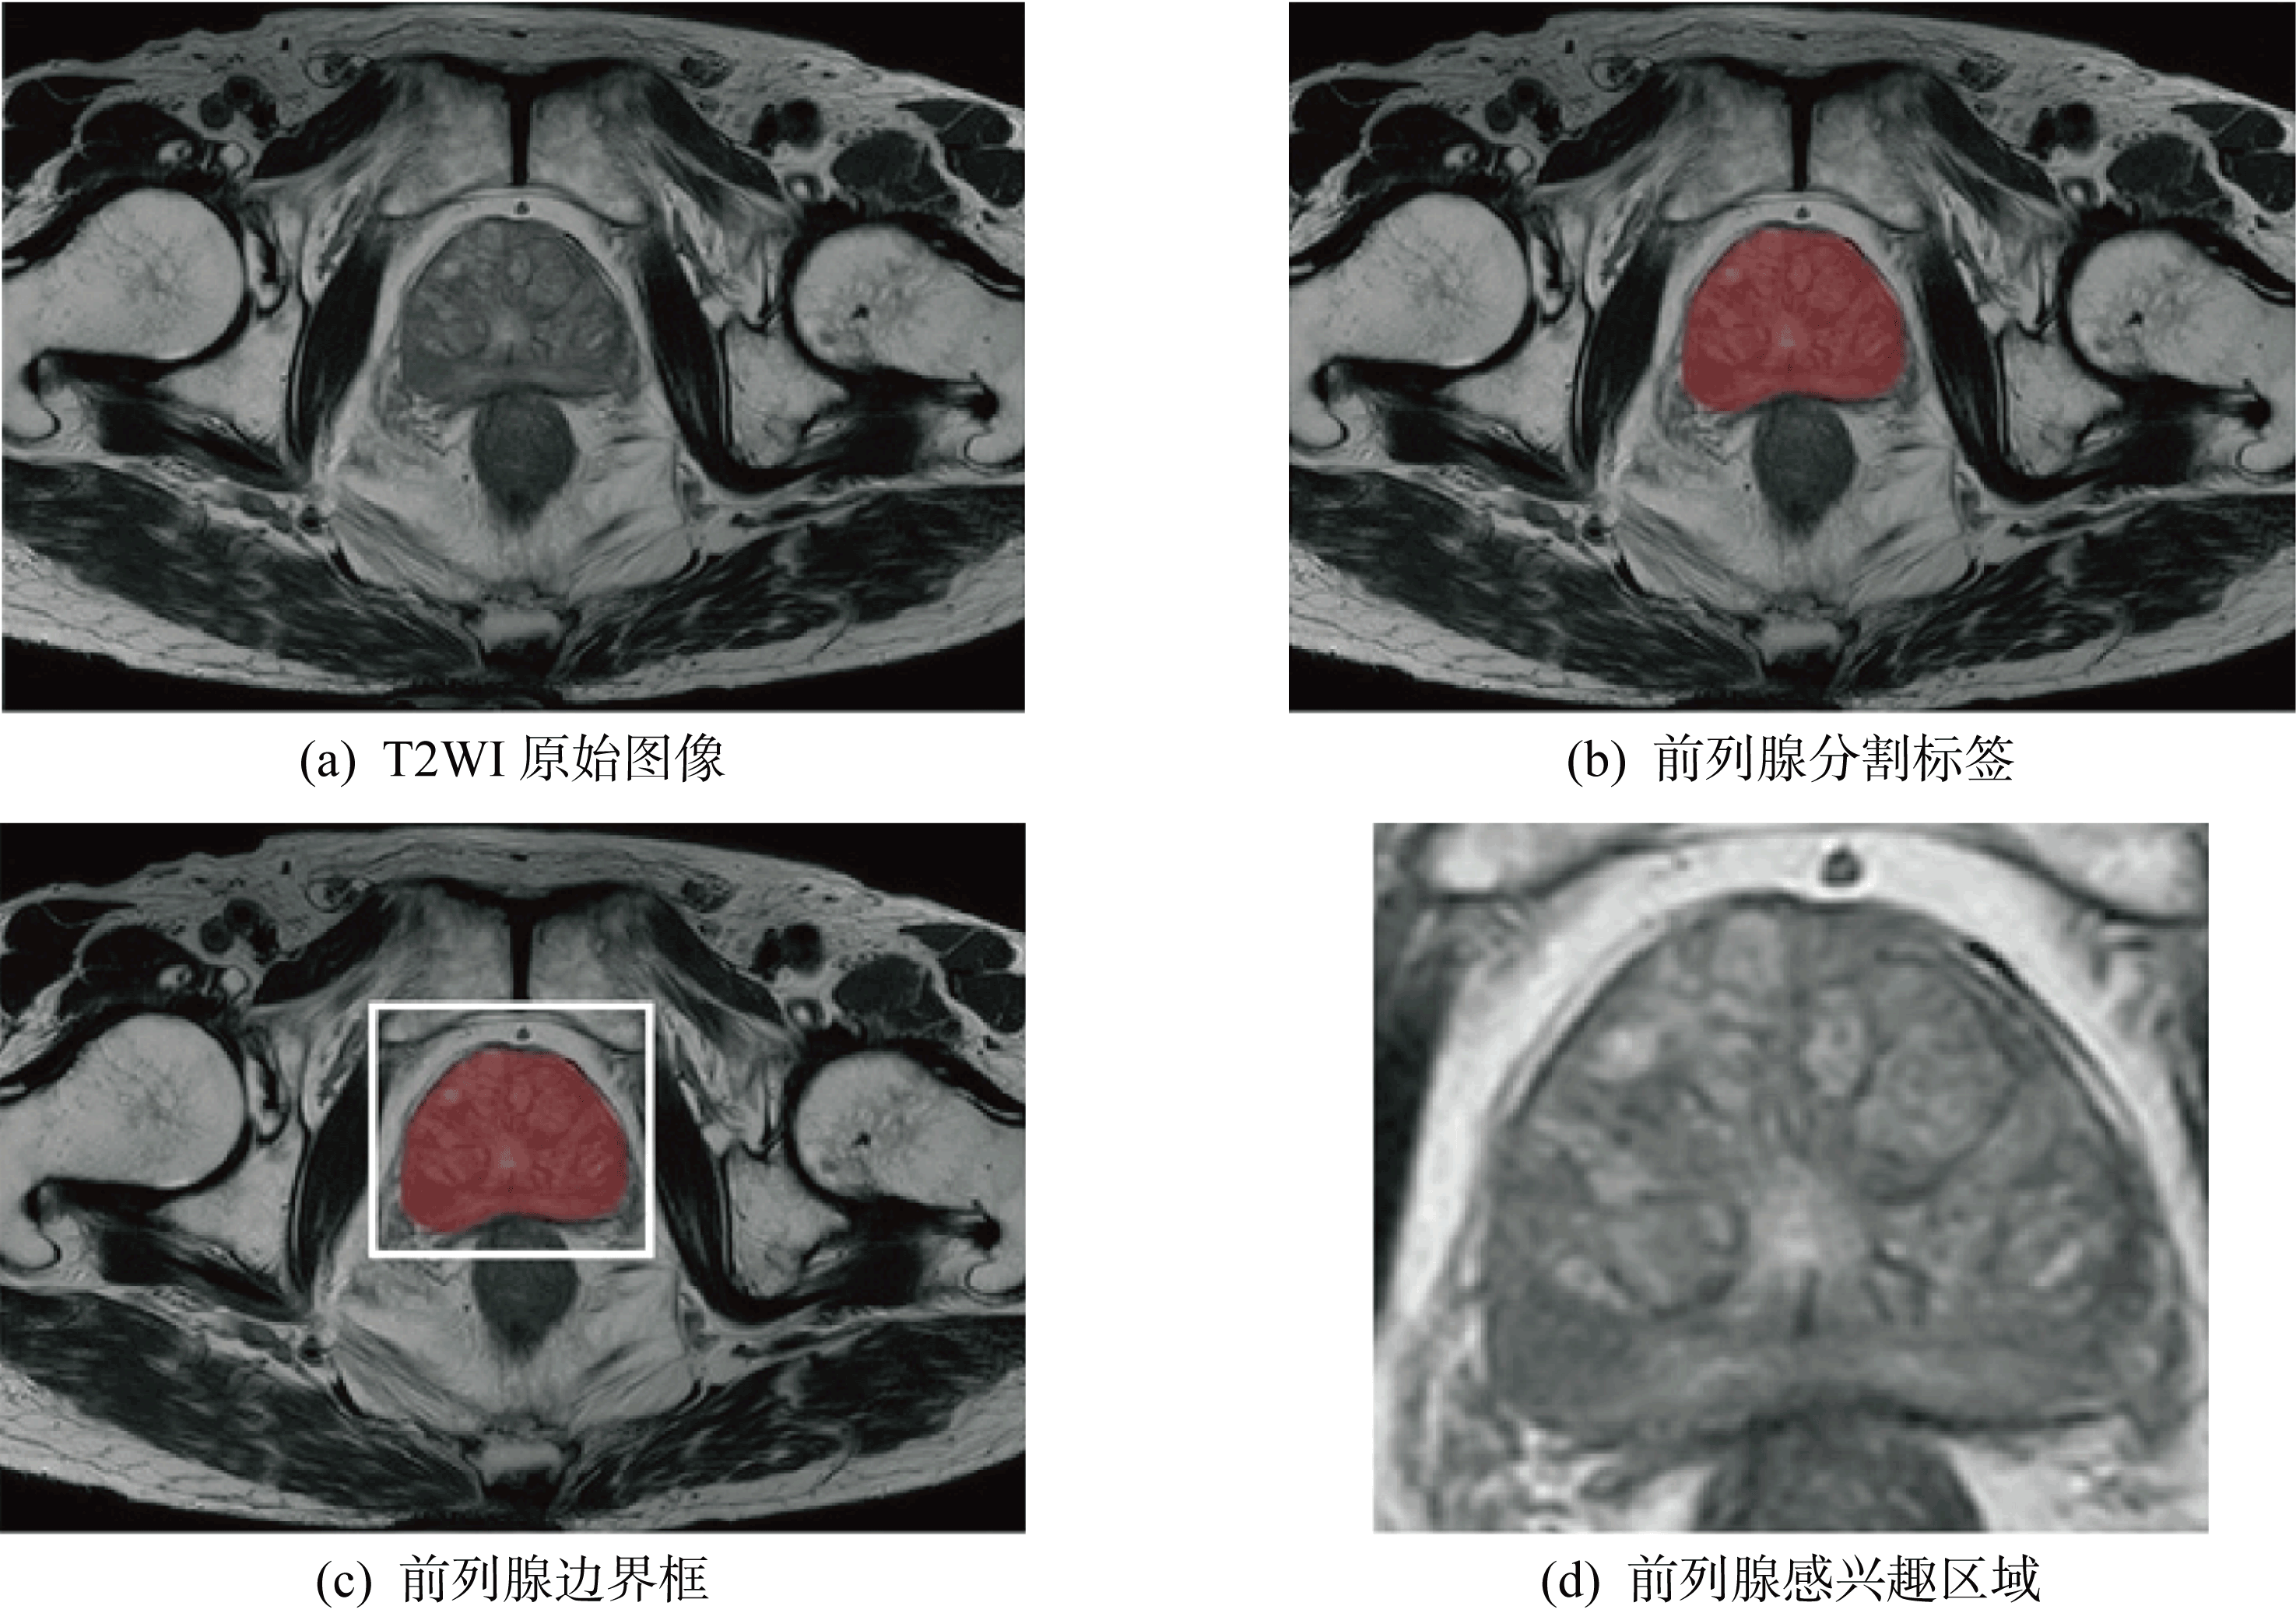

| 图4 感兴趣区域裁剪流程 |

| Fig.4 Flow chart of cropping region of interest |